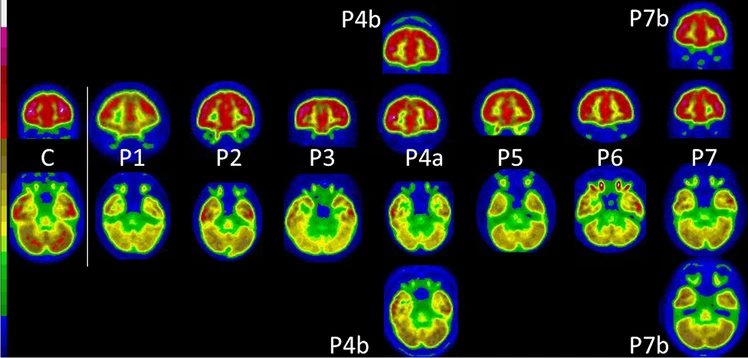

A study looked at PET brain scans of 7 children with Long COVID and compared them to 21 pediatric controls, 35 adults patients with Long COVID and 44 health adult subjects ( link.springer.com ). H/T: @MarcusFitzsimon 8/

Researchers found that despite lower initial severity of COVID-19 infection, pediatric patients had similar brain patterns to adult Long COVID patients on average 5 months later. On the left (C) is the brain scan of a healthy child compared to kids with Long COVID (P1 to P7). 9/

They conclude that children can have Long COVID, "with a similar functional brain involvement to those found in adults, regardless of age and initial severity." 10/